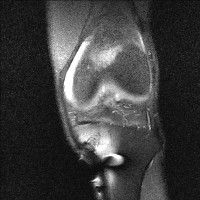

무릎 mri 간단히 봐주실 수 있으시나요 ㅠㅠ

안녕하세요 8년전 십자인대 수술하고 최근 무리한 운동에 무릎 불편감이 생겨서

mri 찍었습니다.

진단결과는 첫 찍은 병원에서 활액막염 이라는 진단을 받았습니다. 혹시 봐주실 수 있으실까요?

올라온 MRI가 단편적이라서 정확한 진단에 어려움이 있지만 십자인대에는 큰 이상이 있지는 않은것 같으며, 무릎관절내 물이 있는 것으로 보아 활액막염의 진단이 맞을 것 같습니다.

하지만 단편적인 영상이기 때문에 촬영병원에서 정확한 판독지 등을 받으시는 것이 좋겠습니다.